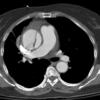

Ao Diss 1a

Date: 01/21/2006

Views: 4075